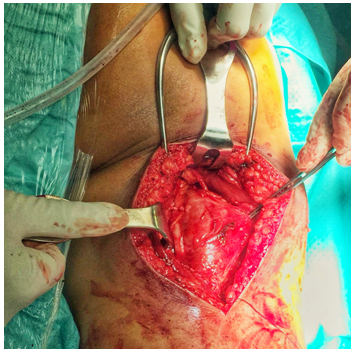

A nodular and whitish-colored tumor was observed next to the sciatic nerve in its most cranial portion of the right thigh. The longitudinal dissection of the peripheral sciatic nerve sheath was performed for complete tumor resection, which was sent to the PA for histological study (Figure 3). The absence of lesion was verified in the proximal and distal ends of the nerve, trying to preserve as many viable nerve fibers as possible.

Figure 3 Intraoperative image: excised tumoral piece.

The PA report showed the presence of nodular tissue of mucinous content and with cystic and hemorrhagic areas, without evidence of malignancy, compatible with the diagnosis of schwannoma.In a postoperative re-evaluation of the functional capacity of the operated limb, parenthesis were observed in the dorsal and lateral face of the leg and foot, besides inability to extend the fingers and to flex dorsally the foot. An electromyogram (EMG) was requested to verify the degree of nerve damage, which showed a damage of 95% of the nerve fibers corresponding to the external popliteal sciatic nerve (EPS) o fibularis communis nerve.